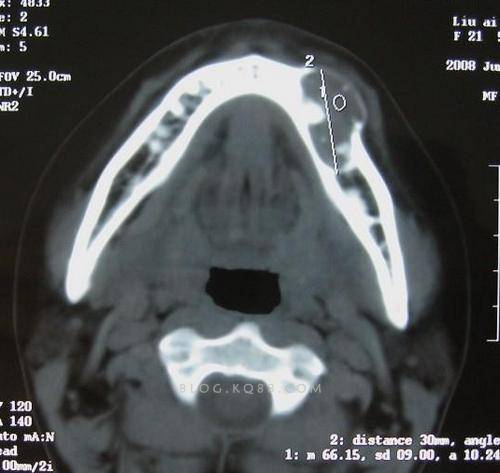

疾病x片

骨化性纤维瘤为颌面骨比较常见的良性肿瘤。临床上骨化性纤维瘤与骨纤维异样增殖症,或称骨纤维结构不良很难鉴别,后者一般认为不是真性肿瘤。

骨化性纤维瘤常见于年轻人,多为单发性,可发生于上、下颌骨,但以下颌较为多见。女性多于男性。此瘤生长缓慢,早期无自觉症状,不易被发现;肿瘤逐渐增大后,可造成颌骨膨胀肿大,引起面部畸形及牙移位。发生于上颌骨者,常波及颧骨,并可能波及上颌窦及腭部,使眼眶畸形,眼球突出或移位,甚或产生复视。下颌骨骨化性纤维瘤除引起面部畸形外,可导致咬合紊乱,有时可继发感染,伴发骨髓炎。

2.CT检查 可见骨皮质内囊状破坏,其间常有增生骨化所致的不规则高密度区,硬化成骨区的CT值500~1400Hu不等,骨皮质不规则增厚,向髓腔内突出致髓腔变形、变小,有时可致髓腔闭塞。